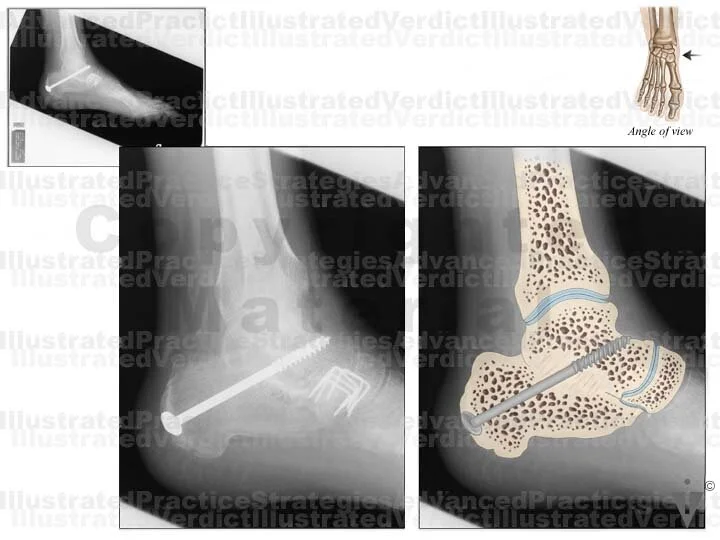

BOARD 18

1. Example film

2. Example film enhancement: open reduction internal fixation of right ankle